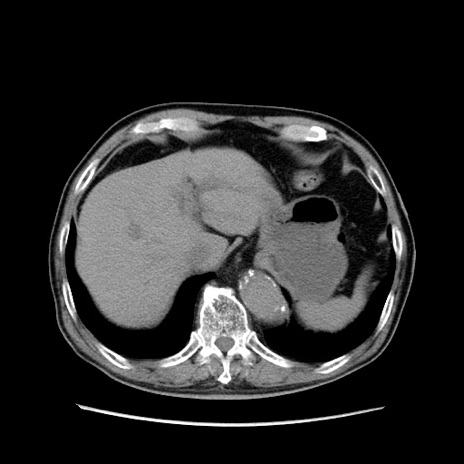

症例24(横断像)

【症例】80歳代男性

【主訴】左側腹部痛、嘔吐

【現病歴】本日早朝より左腹部に痛みあり。昼頃嘔吐認めたため、救急要請。

【既往歴】直腸癌(Mile手術)、胆摘

【身体所見】意識清明、BT 35.9℃、BP 221/93mmHg、SpO2 97%(RA) 、腹部:左ストーマ周囲に限局性の腹部膨隆あり。 膨隆部自発痛・圧痛あり・軟。

【データ】WBC 7700、CRP 0.09